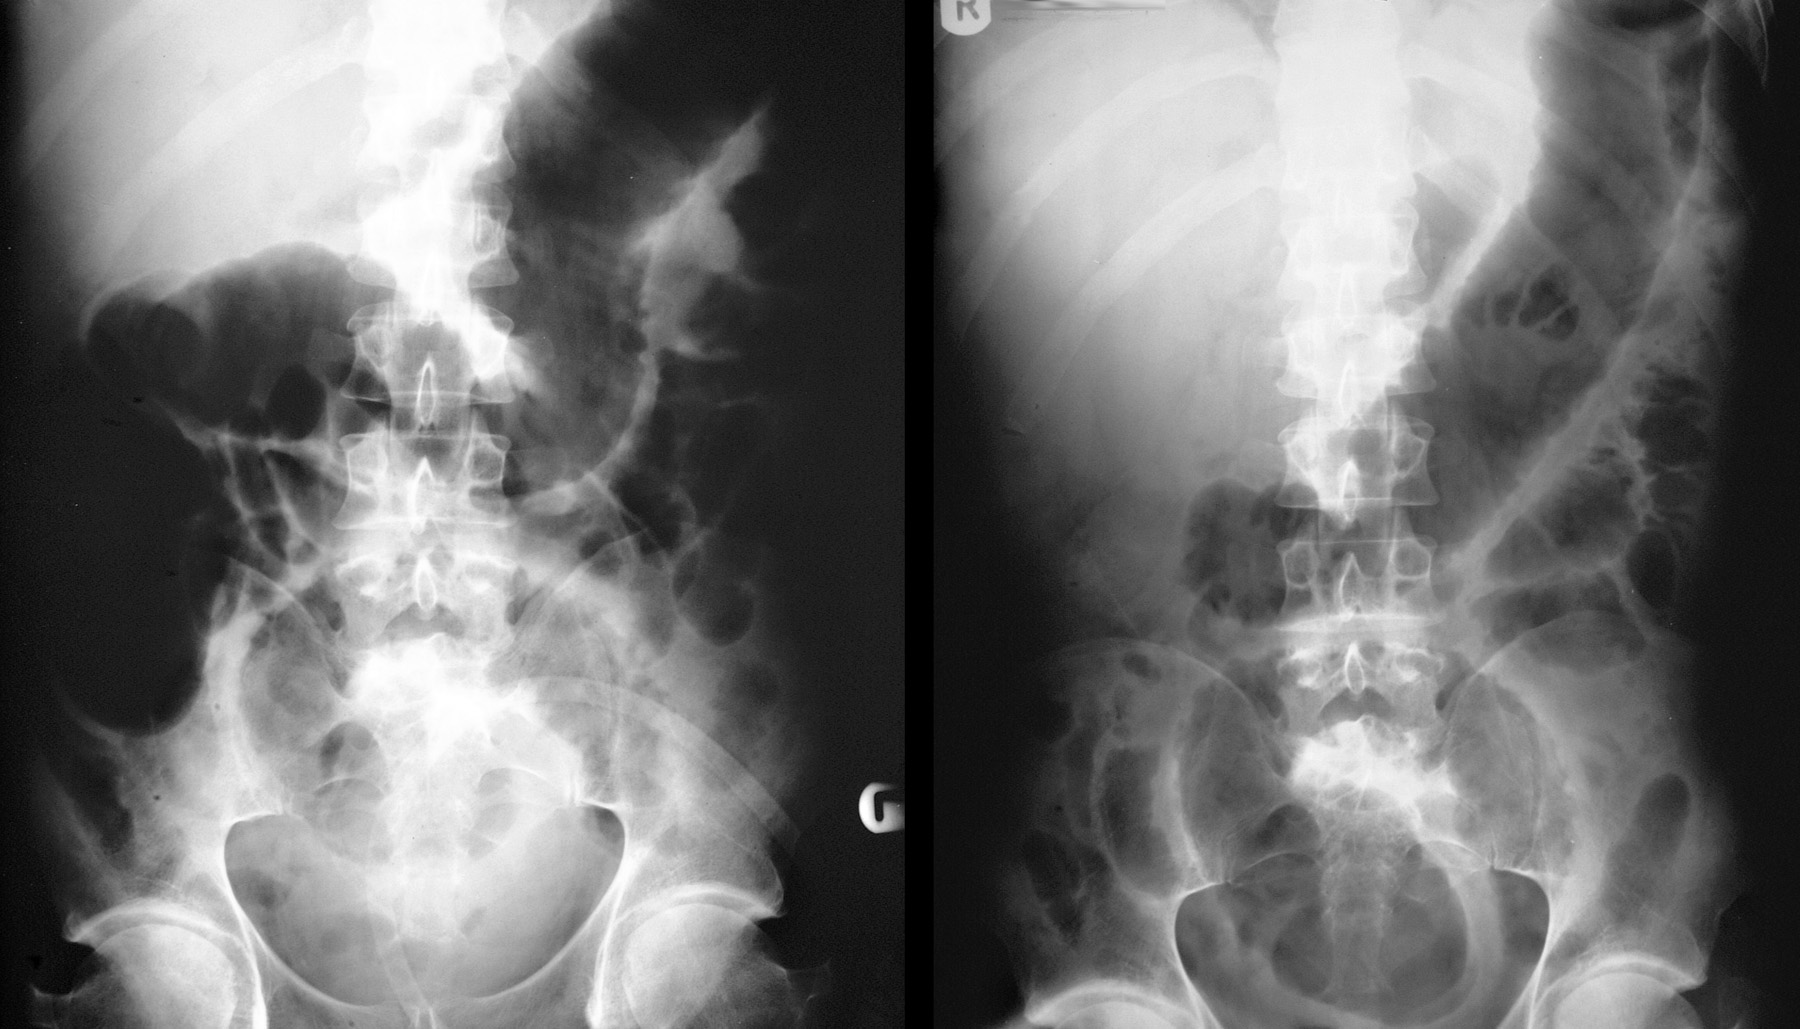

Điều trị Toxic megacolon hay Phình đại tràng nhiễm độc là Xét nghiệm máu toàn bộ (CBC), xét nghiệm bảng chuyển hóa toàn diện (CMP), chụp X-quang, xét nghiệm Lactate, Lipase.